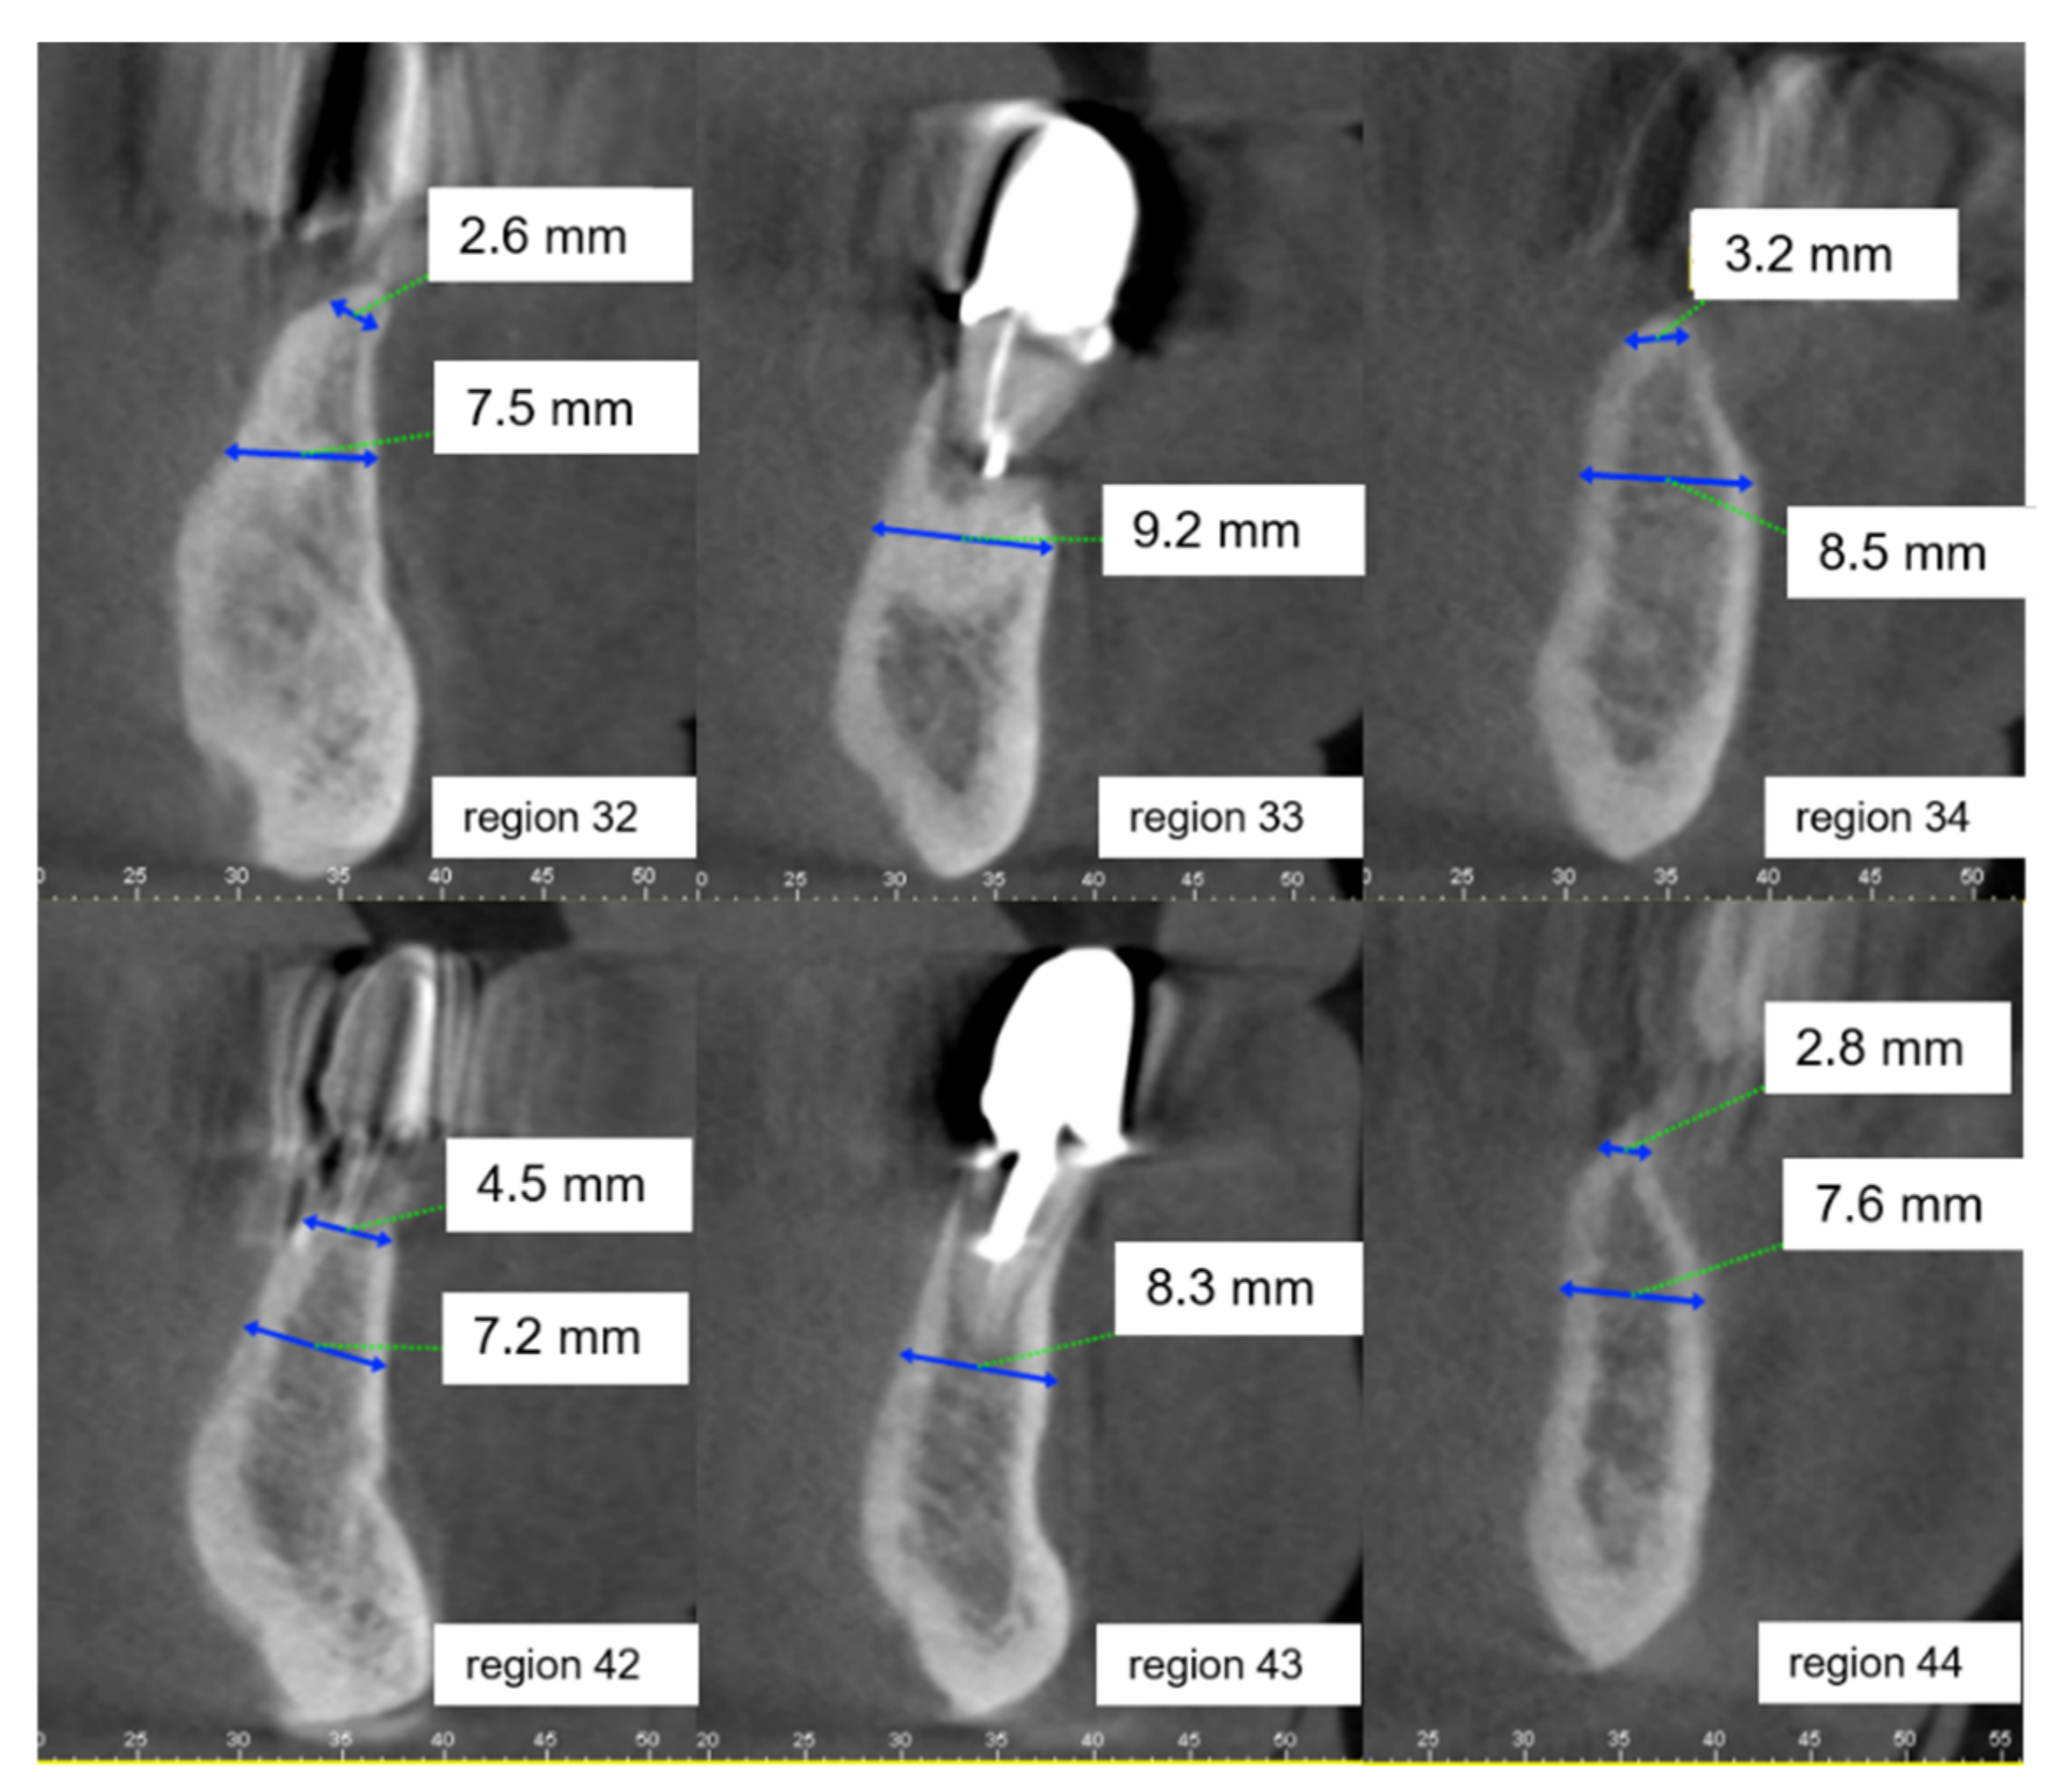

2.2. Clinical Case Vignettes

2.4. Description of the Clinical Case Vignettes